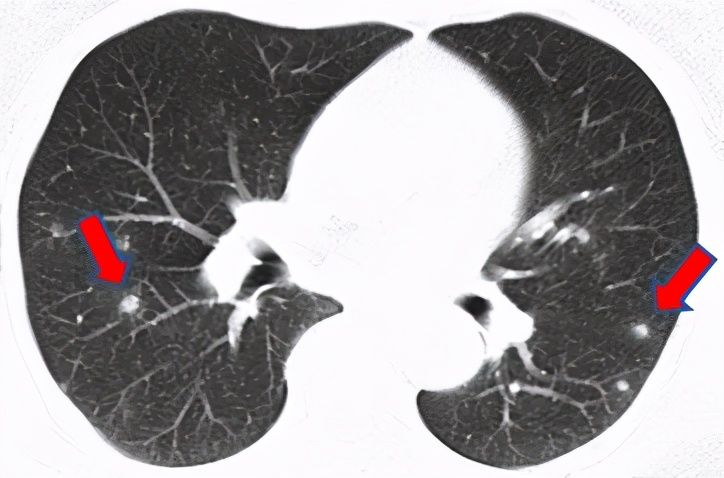

水痘-带状疱疹病毒张奶奶退休后一直在家含饴弄孙。前段时间小家伙被幼儿园同学传染了水痘,发烧出痘折腾了好久,一家人都累坏了。而一波未平一波又起,张奶奶自己又开始咳嗽起来,眼看着咳了一周还不好,查了胸部CT发现双肺有多发小结节。医生建议张奶奶做个支气管镜检查,好明确肺结节性质。

支气管镜检查之后,医生安排把取到的标本做微生物基因检测,竟然检出了“水痘-带状疱疹病毒”。看到报告,不用医生解释张奶奶自己也明白了:在照顾小孙子的过程中她日夜不离,很可能就是在这个过程中吸入了病毒。所幸治疗简单,口服抗病毒药物之后,张奶奶双肺的结节都渐渐吸收了。